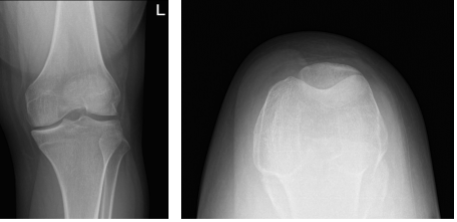

Patient is 19 year-old-male patient with pain in his left knee. It started after he slipped while playing soccer at home. His X-ray were presented and reviewed, though there are no significant degenerative and no acute fracture.

His history and examination are strongly suggestive of ACL rupture with possible lateral meniscus tear left knee. Other symptoms were not present. Further diagnostic testing is required at this time. Patient will move his knee and be WBAT with crutches.

Left knee X-ray complete with patella